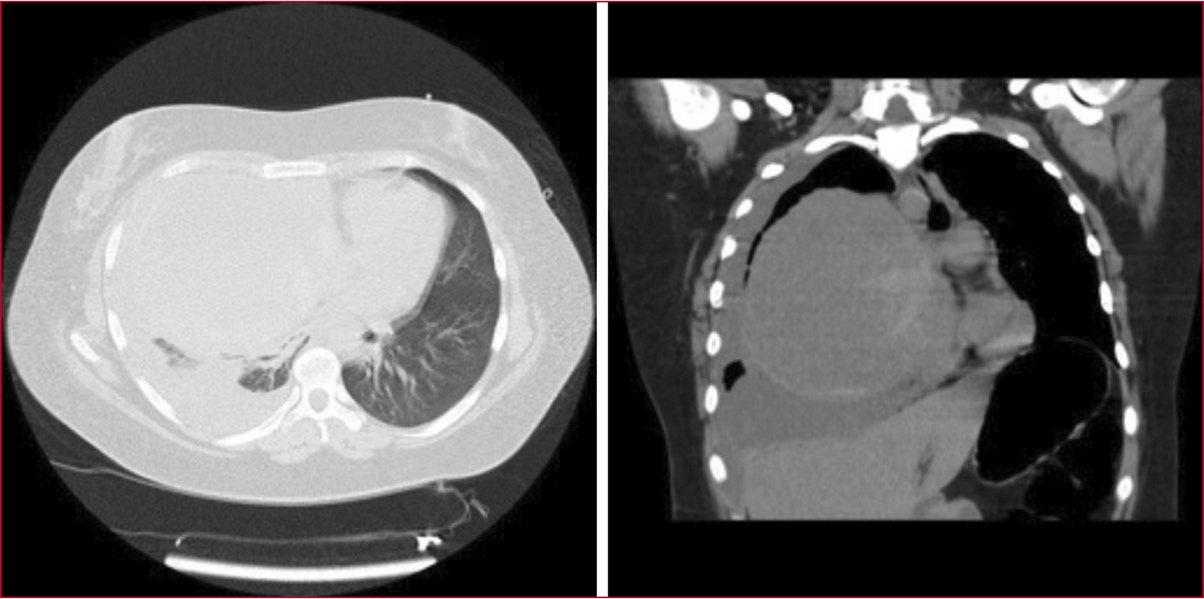

Mujer de 27 años, con antecedente de disnea de tres meses de evolución, tratada inicialmente como asma resistente al tratamiento, quien consulta al servicio de urgencias por disnea de clase funcional III. Se realiza una tomografía computarizada de tórax (Figura 1) que revela una masa tumoral heterogénea y de gran volumen en el mediastino, con efecto de masa en el lóbulo superior derecho desplazando grandes vasos hacia la izquierda e infiltrando el tronco braquiocefálico.

Figura 1. Tomografía computarizada de tórax. Se observa un mediastino levemente desviado hacia la izquierda, debido a una formación ubicada en el mediastino anterior, de paredes gruesas, con algunas calcificaciones aisladas y contenido líquido, de aproximadamente 130 x 118 mm. La imagen también muestra un derrame pleural derecho y líquido laminar perihepático.